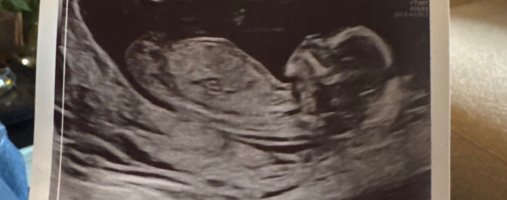

Veldig vanskelig NUB, men tipper jente.En vennine sin, noen som vil gjette![]()

Serbiske NuB dessverre